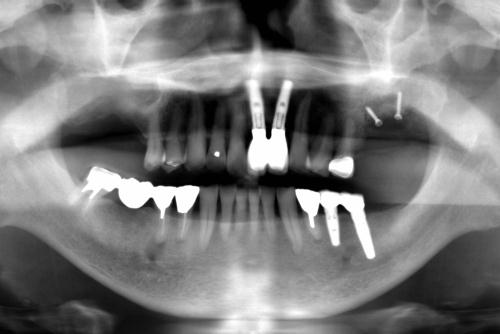

★ デジタルレントゲン設備

放射線量が少ないため、通常のフィルム式レントゲンより1/4~1/10の放射線量と人体に優しく、より鮮明な画像が得られる最新型のデジタルレントゲン装置を導入しています。

また、チェアーサイドにはレントゲン画像などを見ることができる液晶モニターを設置、パソコンなどのIT機器を最大限に活用し診断・治療説明を行っています。